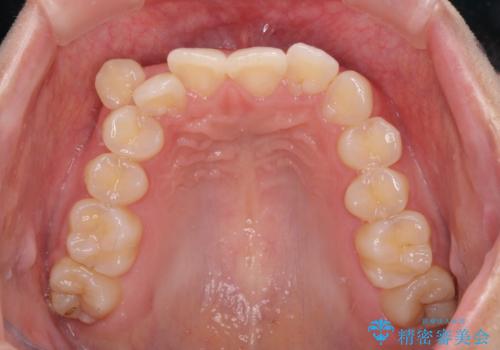

八重歯の抜歯矯正 補助装置とワイヤーを併用したインビザライン矯正治療

- 八重歯と上顎正中のズレを気にして来院された患者様です。

インビザラインによる矯正治療を希望されたため、八重歯改善のための抜歯矯正部分や上顎正中の大幅に位置移動は、補助装置やワイヤー矯正を併用し、その後はインビザラインにて行うこととしました。

骨格的に下顎が左側に変位していたため、上下正中を合わせることは困難であることは分かっていましたが、可能な限り合わせることができました。

骨格的なズレがあると仕上げの段階で奥歯の咬み合わせが不安定となるため、予定よりやや長期間となりました。